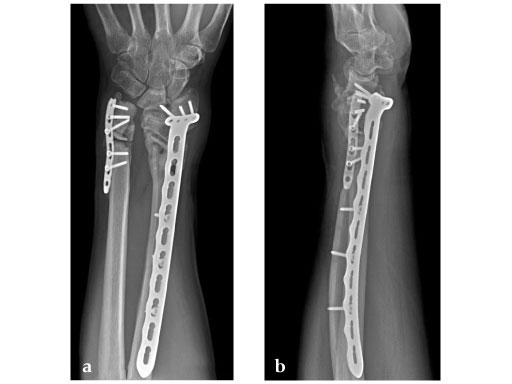

Fig 2ab: Eight months postoperative; full forearm rotation and 75% grip strength and wrist motion.

Fig 3ab: Full motion recovery.

Case provided by Jesse Jupiter, Boston